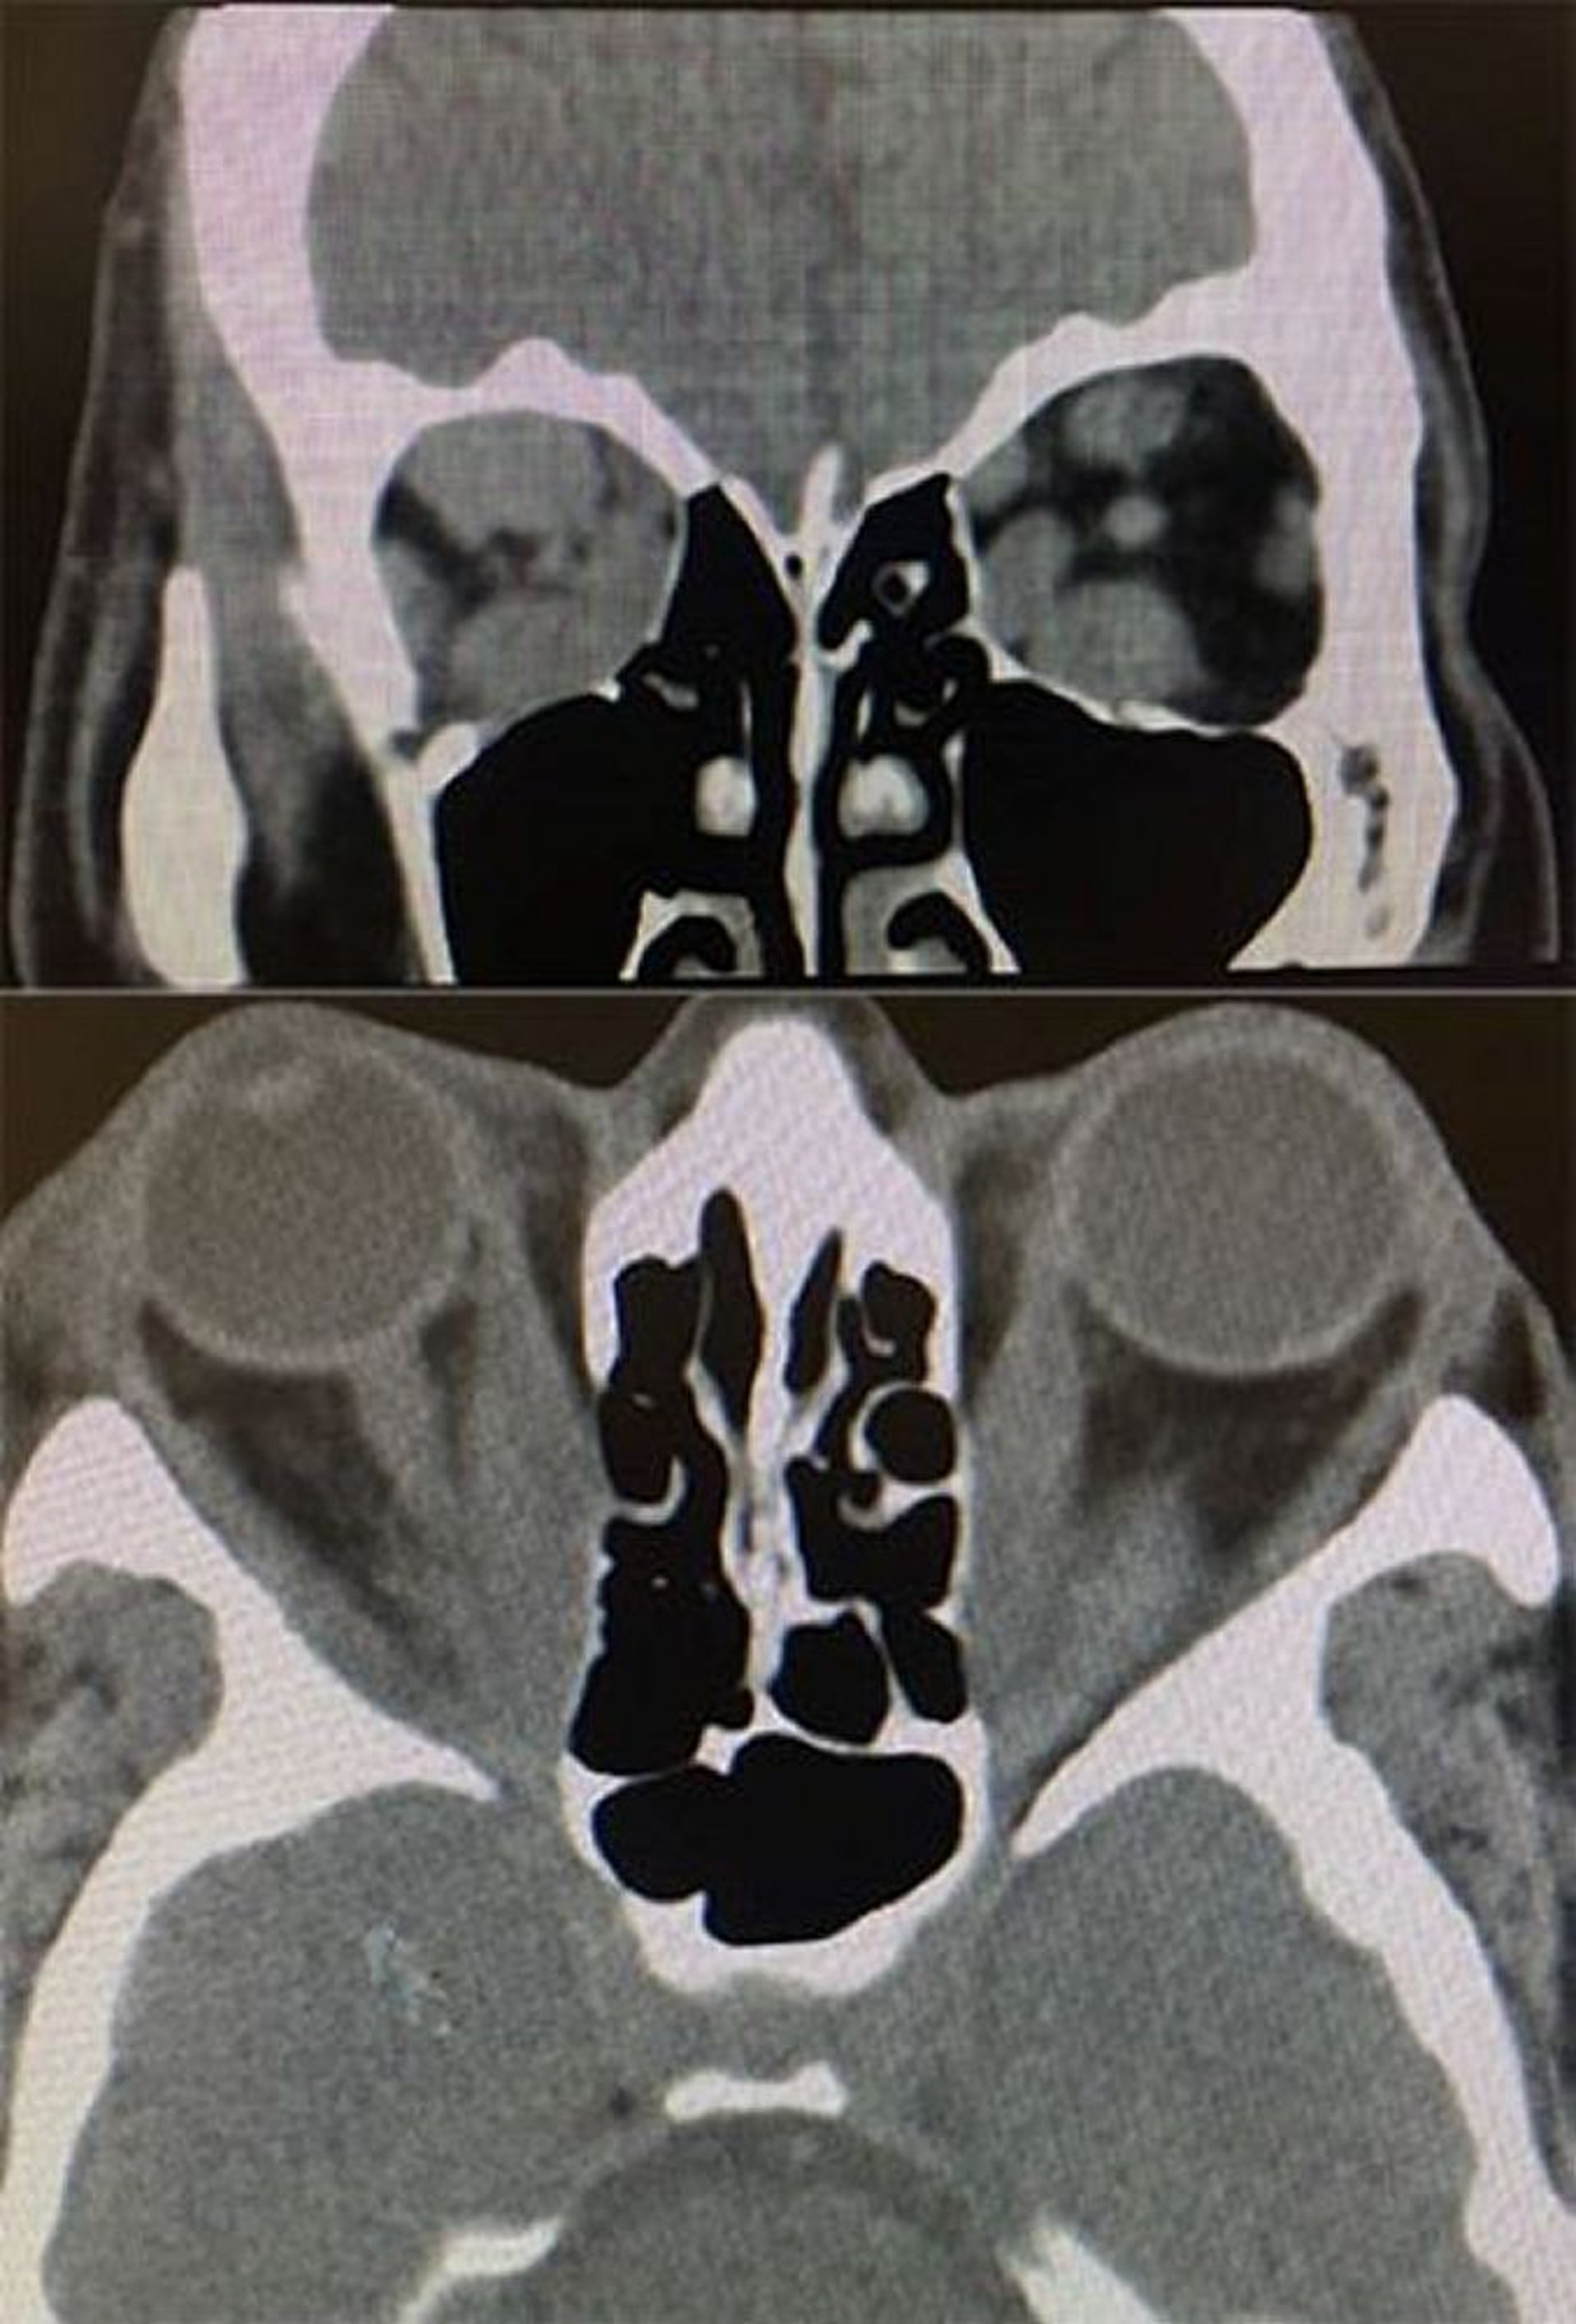

Ophtalmopathie thyroïdienne (TDM)

Dans cette image, les TDM axonales et coronales montrent des signes dans l'ophtalmopathie thyroïdienne. En bas: la TDM axiale montre une hypertrophie qui épargne le tendon du muscle droit médial, bilatéralement. En haut: la TDM coronale montre une augmentation de volume des muscles droit inférieur, supérieur et médial plus à droite qu'à gauche.

Images courtesy of Richard C. Allen, MD, PhD.